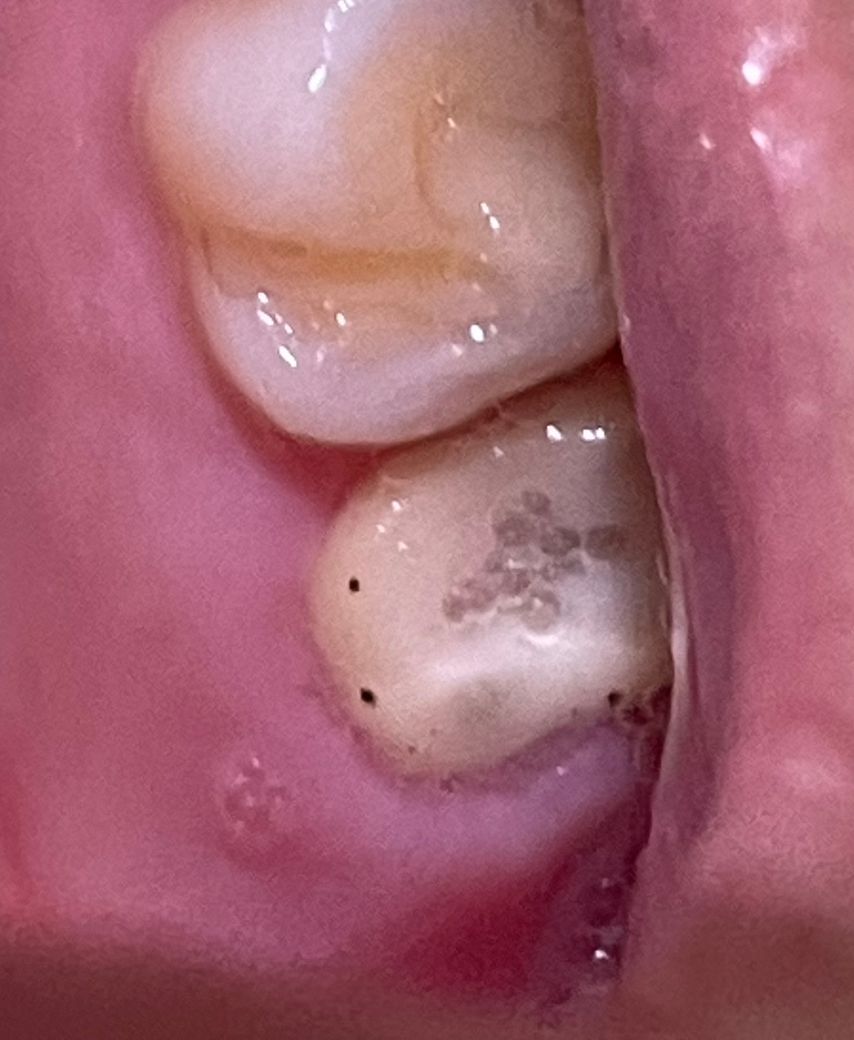

치아에 검은 반점이 생겼습니다(사진있음)

근데 이가 조금 욱씬거리는 듯해서 사진을 찍어봤는데

1) 선으로 표시해둔 검은 반점이 궁금합니다

검은반점이 있고 가운데는 흰색으로 동그랗게 있네요

이건 무엇인가요??ㅜㅜ

2) 검은색 바닐라빈마냥 콕콕 박힌 것들은 무엇인가요?

피딱지인가 싶었는데 면봉으로 닦이지 않습니다

• 1번 째 사진

검은 점들은 교합을 체크할 때 쓰는 교합지로 보이며 내부 검은색은 치아 내부가 그냥 비치는 것 같습니다.

검은색으로 바뀐 점은 레이저로 인해서 다듬어진 연조직일 수 있습니다 이런 것들은 대부분 시간이 지나면서 없었지만 사진에 보이는 치아의 어두운 부분은 치아에 한 부분이기 때문에 크게 걱정하지 않으셔도 될 것으로 보입니다